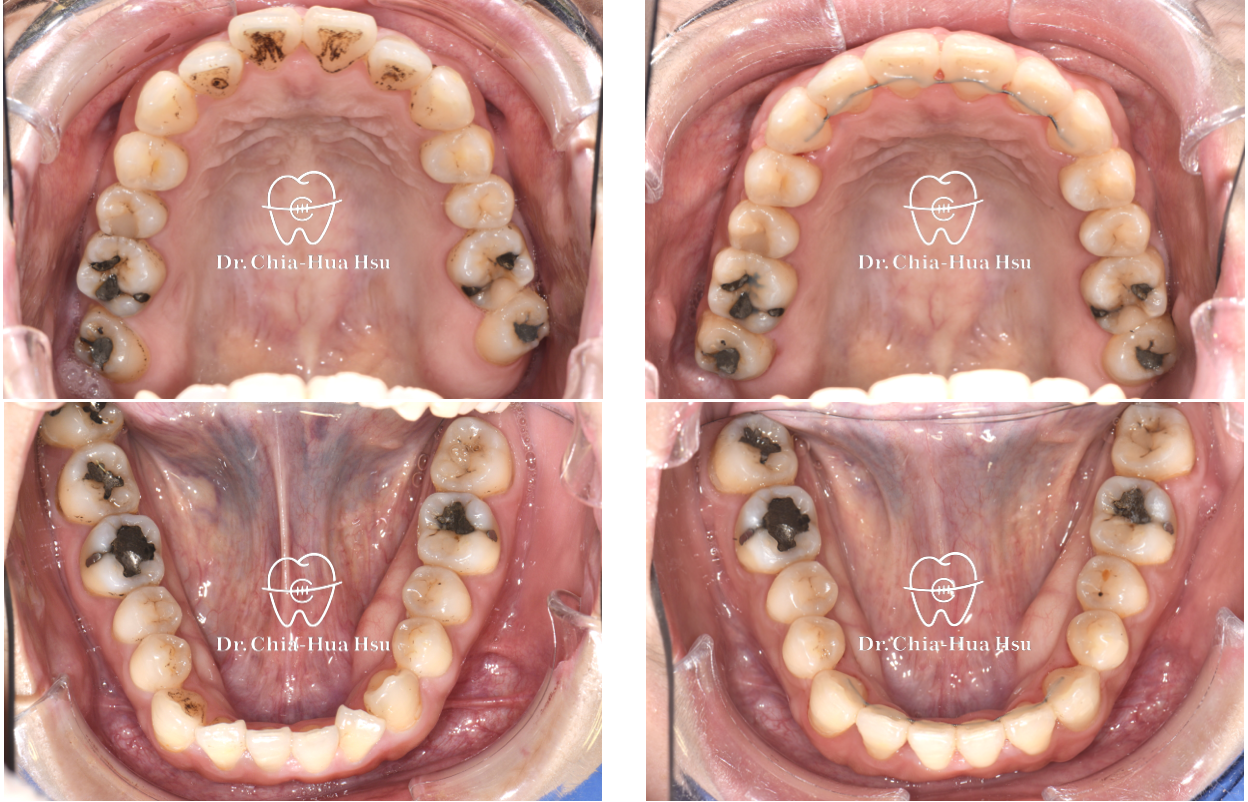

治療前

治療後